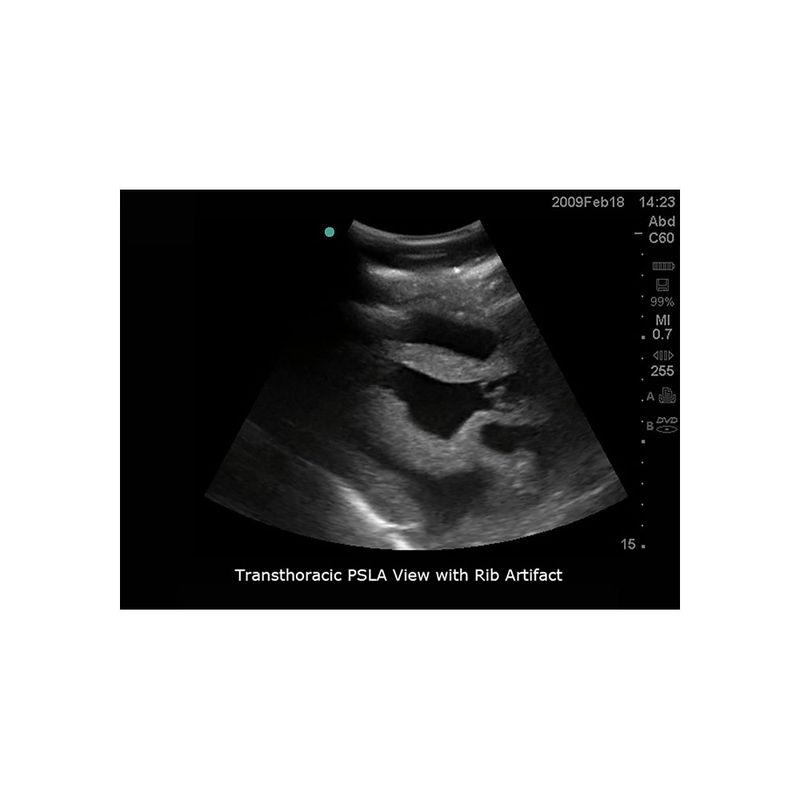

超声引导下心包穿刺术模型

型号:PC-BP003

模型能够与任何带心脏探头的超声影像检查设备连接使用,为练习经胸廓超声引导下心包穿刺训练而设计。